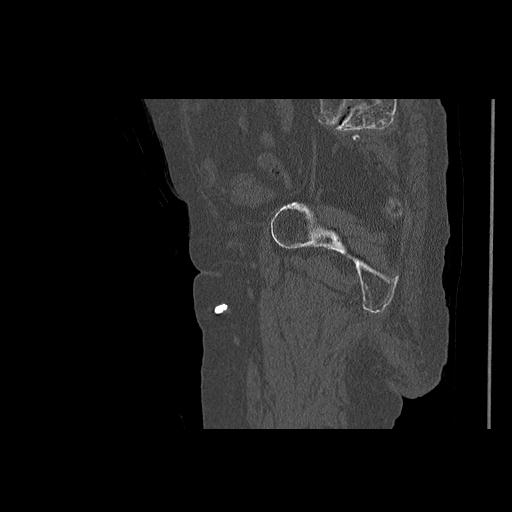

49554 3/13 膝 4R 3/16 4R 1/18 2R 78歳男性 膝蓋骨骨折